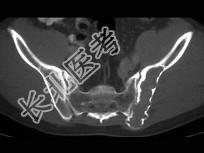

- 单项选择题男,28岁, 左髋疼痛不适三年余,结合图像, 最可能的诊断是 ( )

A、左髂骨动脉瘤样骨囊肿

B、左髂骨单纯性骨囊肿

C、左髂骨骨巨细胞瘤

D、左髂骨棕色瘤

E、左髂骨骨纤维性结构不良